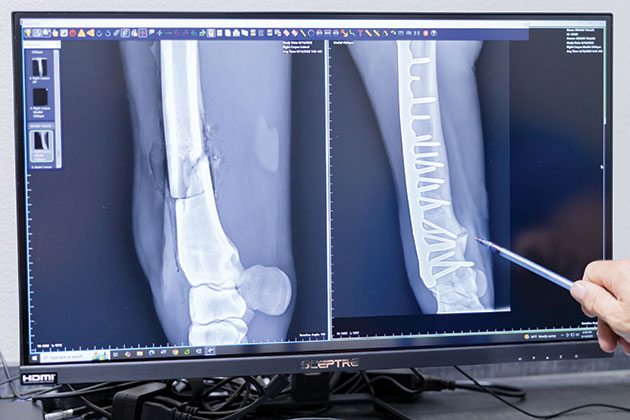

Olecranon (Elbow) Fractures

The olecranon is the bony portion at the upper end of a horse’s ulna bone at the point of the elbow and plays a key role in maintaining the triceps apparatus and thus a horse’s ability to stabilize its leg while standing. “It’s a long bone that is not directly weight-bearing. It’s attached to the radius, which gives us some biomechanical advantages compared to some of the other long bones in the horse,” says Dr. José García-López, an associate professor of large animal surgery at the University of Pennsylvania School of Veterinary Medicine’s New Bolton Center. In some cases these fractures can be non-surgical, but more often surgery is required for an optimal outcome. “This is one of the most common long bone fractures that we see, and it’s not necessarily restricted to one type of athletic work or discipline,” says García-López, VMD, DACVS, DACVSMR. Olecranon fractures can be the result of a kick and can present as an open or closed fracture, with an open fracture posing more risk for complications due to potential wound infection.

Over time, veterinary medicine has standardized a best practices approach to surgical correction. “In most of these cases, we place one, maybe two plates,” explains Dr. García-López. “If there are multiple pieces or if we’re dealing with a 550-600 kilogram (roughly 1,200-1,300 pound) horse with enough fragmentation, we can worry that one plate alone may not do the job. The caudal aspect of the olecranon or the ulna is the tension surface of the bone — it handles the continuous pulling of the triceps. From a biomechanical standpoint, this is why a plate (implant) is typically the strongest choice.” He places significant emphasis on biomechanics and the nuances of each fracture’s configuration to make the best choice for implant number and type. “Which type of bone are we dealing with? Can the repair be placed in the tension surface or the bending surface of the bone?” he asks. “If we’re dealing with a bending surface and we choose to use an implant, we’re going to fatigue that implant just by the nature of how much bending it will experience; that implant will be much more prone to failure. However, by placing an implant in a location that experiences constant tension and pulling — such as the triceps — an implant will become quite strong.” When dealing with the back, or caudal, surface of the bone, a relatively small plate can be the right option for the scenario, rather than a large implant. “If we chose that same plate for a different long bone, it would likely fail, but here the horse would have a good chance,” he says of a generalized prognosis for olecranon fractures. “Overall, we’ve done a pretty good job at getting these horses back to work. These cases can be challenging, and the recovery process as we bring the horse out of anesthesia is critical to avoid failure, but we’ve gotten some good numbers in terms of getting these horses back to performance successfully.”